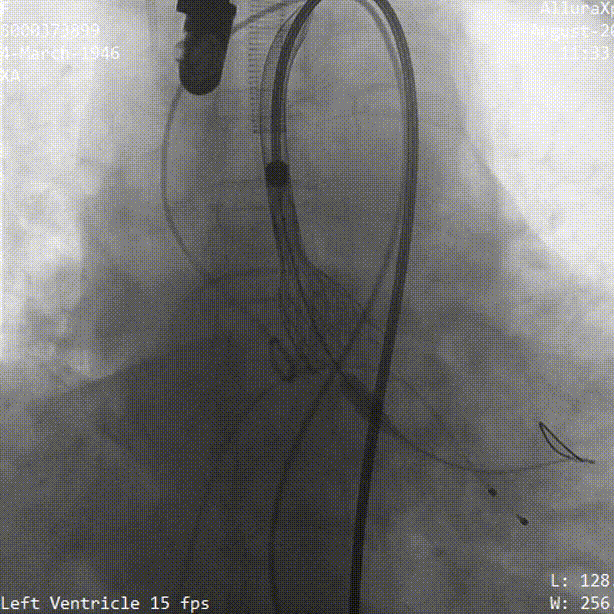

瓣膜稳定脱钩过程

最终位造影 形态良好 位置理想

无瓣周漏 即刻跨瓣压差为3mmHg